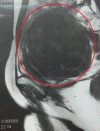

美容・健康 38歳女、「子宮筋腫」手術の体験レポ 子宮筋腫、摘出手術の体験記【腹腔鏡手術】――やってよかった? 術後1カ月before/after 40代女性の3~4人に1人は抱えている子宮筋腫。下腹が出たり、頻尿や貧血になったりと、生活の質は下がるが、命には別状はないため、手術まで踏み切... 健康 2019/03/23 19:00

美容・健康 38歳女、「子宮筋腫」手術の体験レポ 子宮がん検診で“しこり”12センチ発覚! 38歳で「子宮筋腫」手術を決意したワケ 40代女性の3~4人に1人は抱えている子宮筋腫。下腹が出たり、頻尿や貧血になったりと、生活の質は下がるが、命には別状はないため、手術まで踏... 健康 2019/03/22 19:00